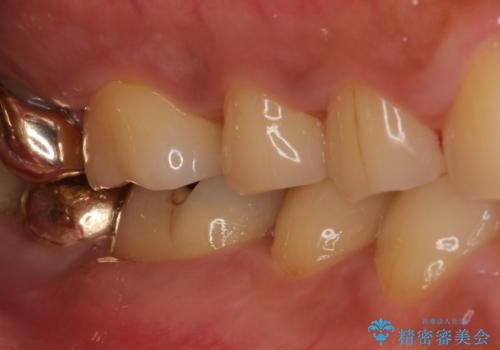

ゴールドインレーは銀歯のインレーやセラミックインレーと比べ、「技工操作の精度が高く、適合が著しく良い」というメリットがあります。特に上の奥歯は歯科医師の操作が行いにくいため、「適合の良さ」は再治療のリスクを防ぐ上でとても重要な要素となります。

上の奥歯は金属色が見えることもないため、審美的な問題は全くありません。

咬み心地はとても良好で、全く違和感がなく、患者様には大変満足していただきました。